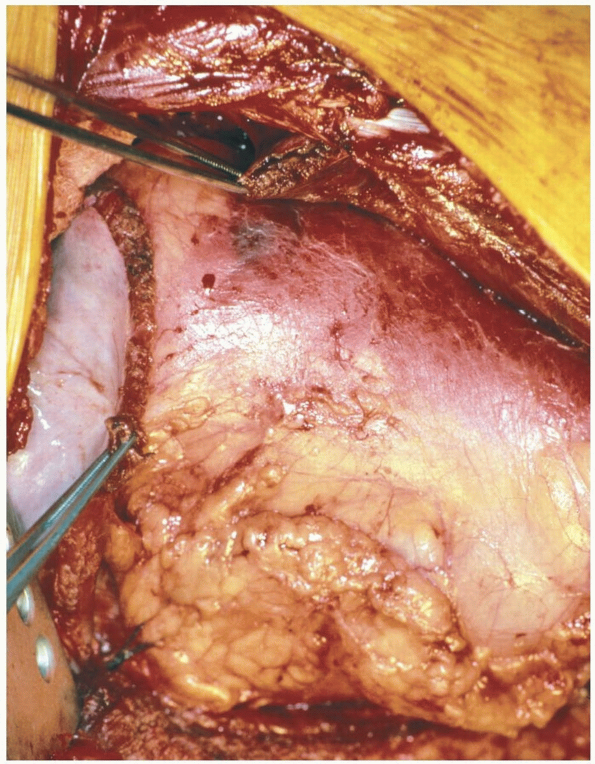

We typically position the patient with left side up so

as to avoid the interference with the liver. Stabilization is achieved

with radiolucent bolsters, the right hip is flexed and the left hip

extended. Taping of the pelvis and shoulder region reduces

intraoperative rolling of the patient. Thoracotomy can also be

accomplished in the prone position through a traditional anterolateral

approach with the arms in the abducted position most commonly used (Fig. 13-14).

Technique

Incision: the curvilinear incision enters

through the 9th to 11th ribs depending on the pathology and anticipated

length of exposure (Fig. 13-15).

The extensile thoracoabdominal approach is typically carried out

cephalad to the 9th rib so as to allow for a direct visualization of

the dorsal diaphragmatic attachment. -

The latissimus dorsi muscle is split and dissection carried down to the intercostal area.

The dissection is carried over the rib to

protect the neurovascular bundle as in a standard thoracotomy fashion,

but with the patient in a prone position. -

The rib is exposed subperiosteally and as the intercostal nerve and vessels are protected, it is resected (Fig. 13-16).

-

A chest wall retractor is inserted and

with clipping and/or tying of intercostal vessels and with gradual

spreading, the thoracic contents are retracted away from the spine.-